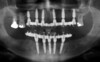

Son cliché panoramique montre de nombreuses infections dentaires et parodontales ingérables.

Le cliché panoramique montre le bon ajustage des pièces en titane et du bridge provisoire en résine armé par des fibres de verre.

Le cliché panoramique permet d’apprécier l’ajustage des armatures usinées sur les piliers et la différence de contraste radiologique entre la zircone au maxillaire et le titane à la mandibule.